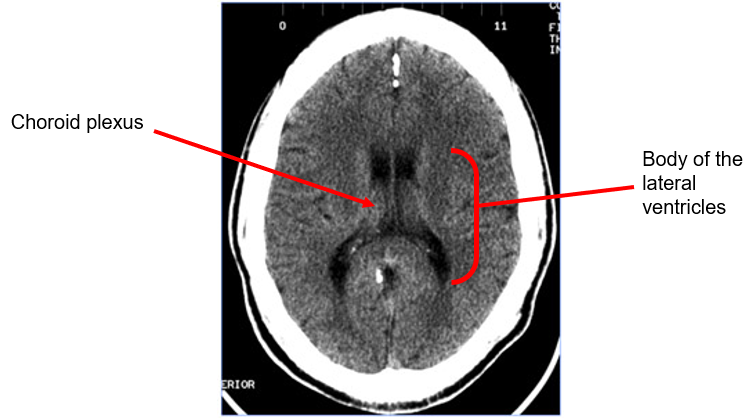

what are the ventricles

•2 (large) c-shaped lateral ventricles

•Third ventricle is narrow cavity in the midline

•Fourth ventricle located between brainstem and cerebellum

Cerebrospinal fluid (CSF): produced in the choroid plexus (lateral ventricles) - exits along the interventricular foramen (of Monro) into the third ventricle[5].

The third ventricle communicates with the fourth ventricle via the cerebral aqueduct, which courses through the midbrain.

Axial CT image of the brain at the level of the body of the lateral ventricles